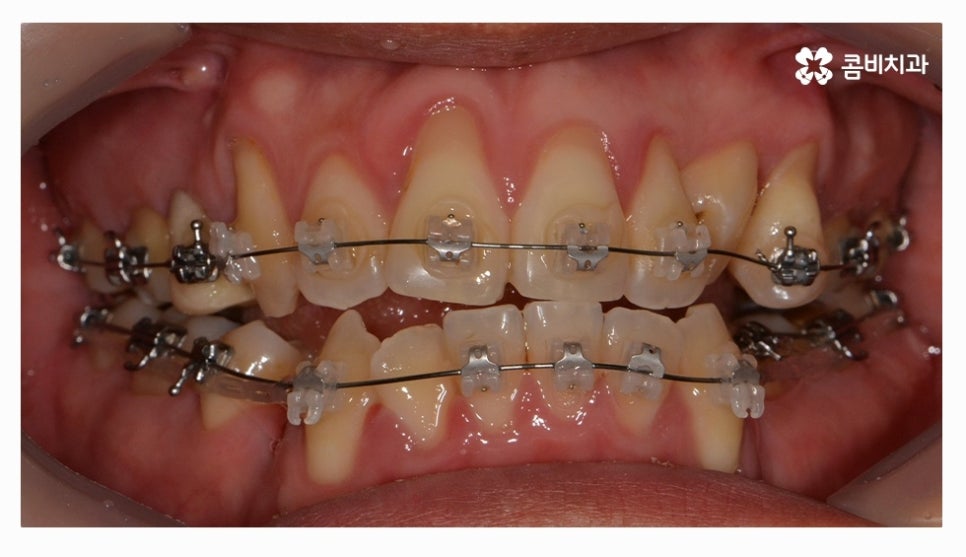

전체교정을 하시는 분들의 경우 보편적으로 많이 선택하시는

교정 장치는 클리피씨교정이라고 할 수 있을 정도로 선호도가 높으며

클리피씨교정은 자가 결찰 장치로 통증 감소 및 교정 기간을

단축시킬 수 있으며 관리가 편리하다는 장점도 갖고 있어요

클리피씨교정은 세라믹 재질이기 때문에 심미적으로도 우수한 편이며

브라켓과 와이어 고정을 위한 철사를 사용하지 않기 때문에 철사로 인해 찔리거나

입안이 뜯겨 피가 나는 경우를 예방할 수 있는데요.

클리피씨교정은 철사를 쓰지 않고 특수 클립이 내장되어

클립을 이용하여 와이어를 고정하고 열고 닫을 수 있기 때문에

교정 장치로 인한 불편함이 줄어들 수 있으며 철사를 사용하지

않는 것만으로도 보다 편안함을 느낄 수 있지만 치아를 적은 힘으로

지속적으로 이동시켜서 상대적으로 통증이 적고 치과 내원 횟수도 줄일 수 있어요.